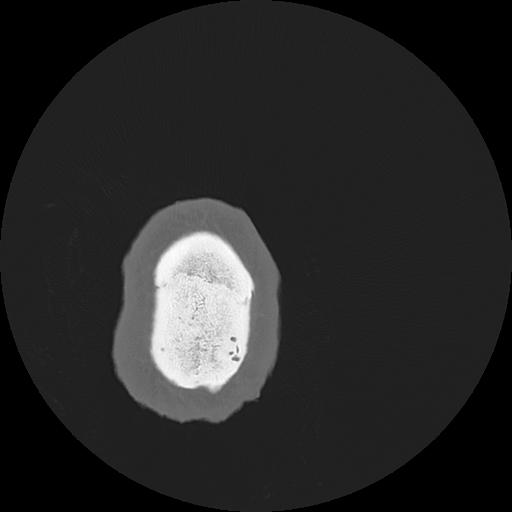

7 HUESO,,Vol,0.5,HUESO,,